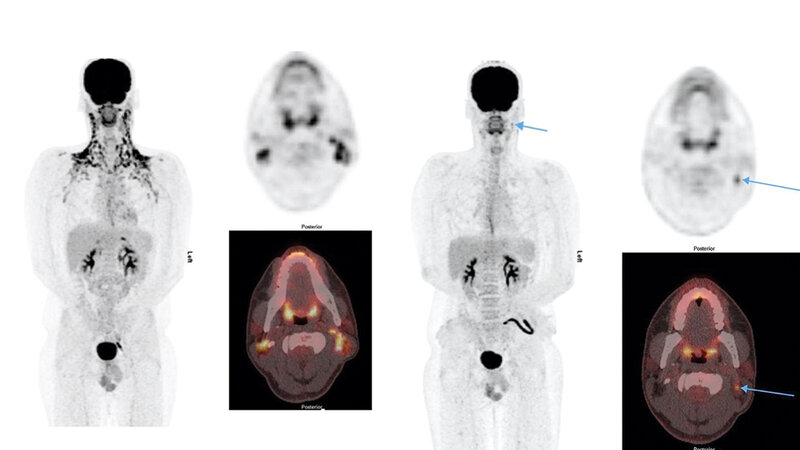

Aktiviertes braunes Fettgewebe beeinträchtigt die Auswertbarkeit von 18F-FDG-PET-Untersuchungen. Dies kann besonders bei jungen Lymphompatienten problematisch sein, bei denen die 18F-FDG-PET eine wichtige Rolle im Behandlungsmanagement spielt. Um aktiviertes braunes Fettgewebe zu verhindern, empfehlen das EuroNet-PHL-C2-Studienprotokoll und die entsprechenden Leitlinien nuklearmedizinischer Fachgesellschaften, den Patienten zu wärmen und vor der Radiotracerinjektion einen nicht selektiven Beta-blocker zu verabreichen. Um herauszufinden, ob und in welcher Weise diese Präventionsmaßnahmen durchgeführt werden, wurden insgesamt 40 PET-Zentren in ganz Deutschland befragt. Daraus resultierte eine unerwartet große Bandbreite an unterschiedlichen Herangehensweisen, die Potenzial für Anpassungen aktueller Empfehlungen/Richtlinien bietet und den Boden für weitere Forschungsarbeiten bereitet.

Activated brown adipose tissue impairs the readability of 18F-FDG-PET scans. This can be particularly problematic in lymphoma patients in whom 18F-FDG-PET plays an important role in treatment management. To prevent activated brown adipose tissue, the EuroNet-PHL-C2 study protocol and respective guidelines of nuclear medicine societies recommend to warm the patient and to administer a non-selective beta-blocker prior to radiotracer injection. In order to determine whether and how prevention measures are performed, a total of 40 PET centres throughout Germany were surveyed. This resulted in an unexpectedly wide range of different approaches which offer potential for adaptation of current recommendations/guidelines and furthermore provide the ground for further research work.